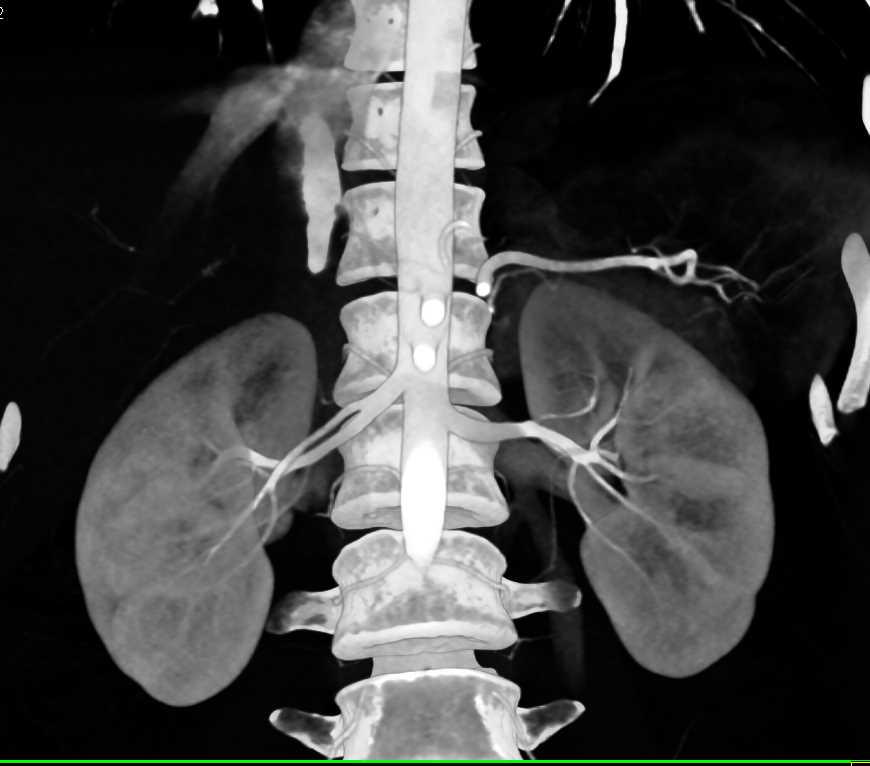

Angiomyolipoma Left Kidney in a Patient With Lymphoma